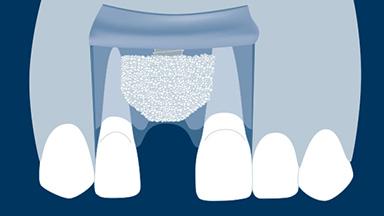

When a tooth is extracted, the alveolar bone that supports the tooth resorbs over time. This resorption results in a reduction in alveolar bone volume, as shown in this clinical example of a missing upper right central incisor. The bone has diminished significantly in orofacial width, and this is in conflict with the fundamental requirement in implant dentistry that implants are placed in the correct prosthodontically determined position. When the alveolar bone resorbs, it is often necessary to augment the bone to ensure that implants can be placed correctly and be completely embedded in bone. This module will describe a specific technique for bone augmentation known as guided bone regeneration or GBR.